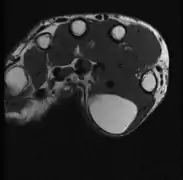

A physical exam is typically the easiest way to diagnose it. Rarely, a tissue biopsy or imaging may be required. The imaging modality of choice is magnetic resonance imaging (MRI) because it has superior sensitivity of distinguishing it from liposarcoma as well as mapping the surrounding anatomy.[22]

The presence of multiple lipomas, lipomatosis, is more commonly encountered in men. Some superficial lipomas can extend into deep fascia and may complicate excision. Liposarcoma is found in 1% of lipomas and is more likely to occur in lesions of the lower extremities, shoulders, and retroperitoneal areas. Other risk factors for liposarcoma include large size (>5 cm), associated with calcification, rapid growth, and/or invasion into nearby structures or through fascia into muscle tissue.[39]